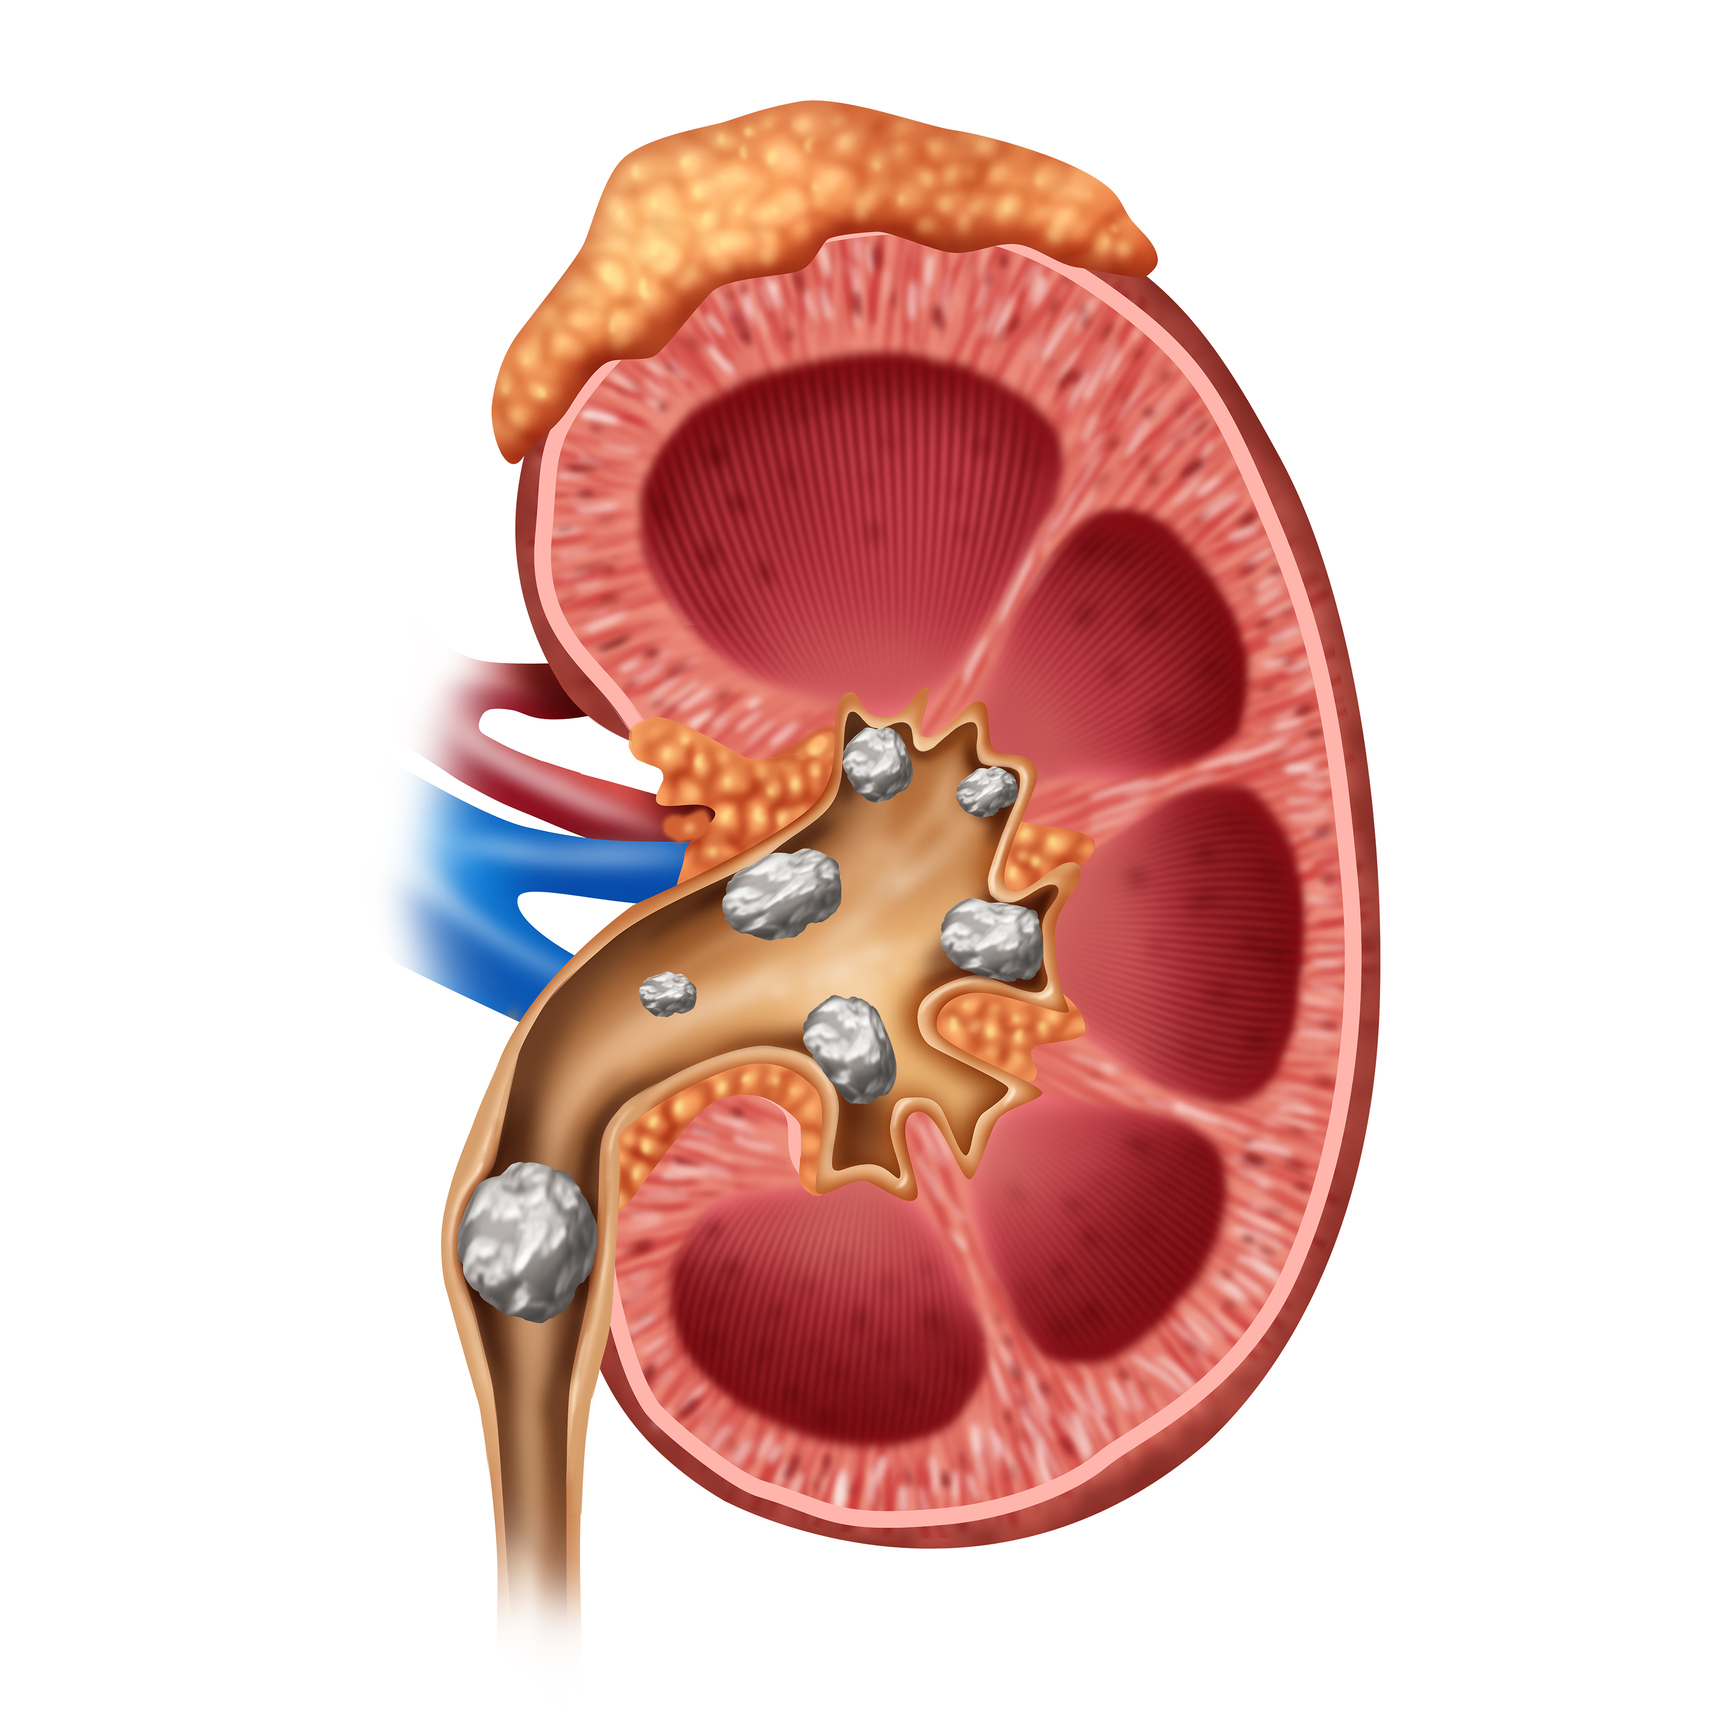

Dehydration can lead to kidney stones, kidney failure, and cardiac arrest

Dehydration can lead to kidney stones, kidney failure, and cardiac arrest. The risk of dehydration is much higher in the summertime, as the weather is hotter and people are outdoors and being active more often. While running low on liquid intake is usually associated with weakness and malaise, you should also know without proper hydration ...click here to read more